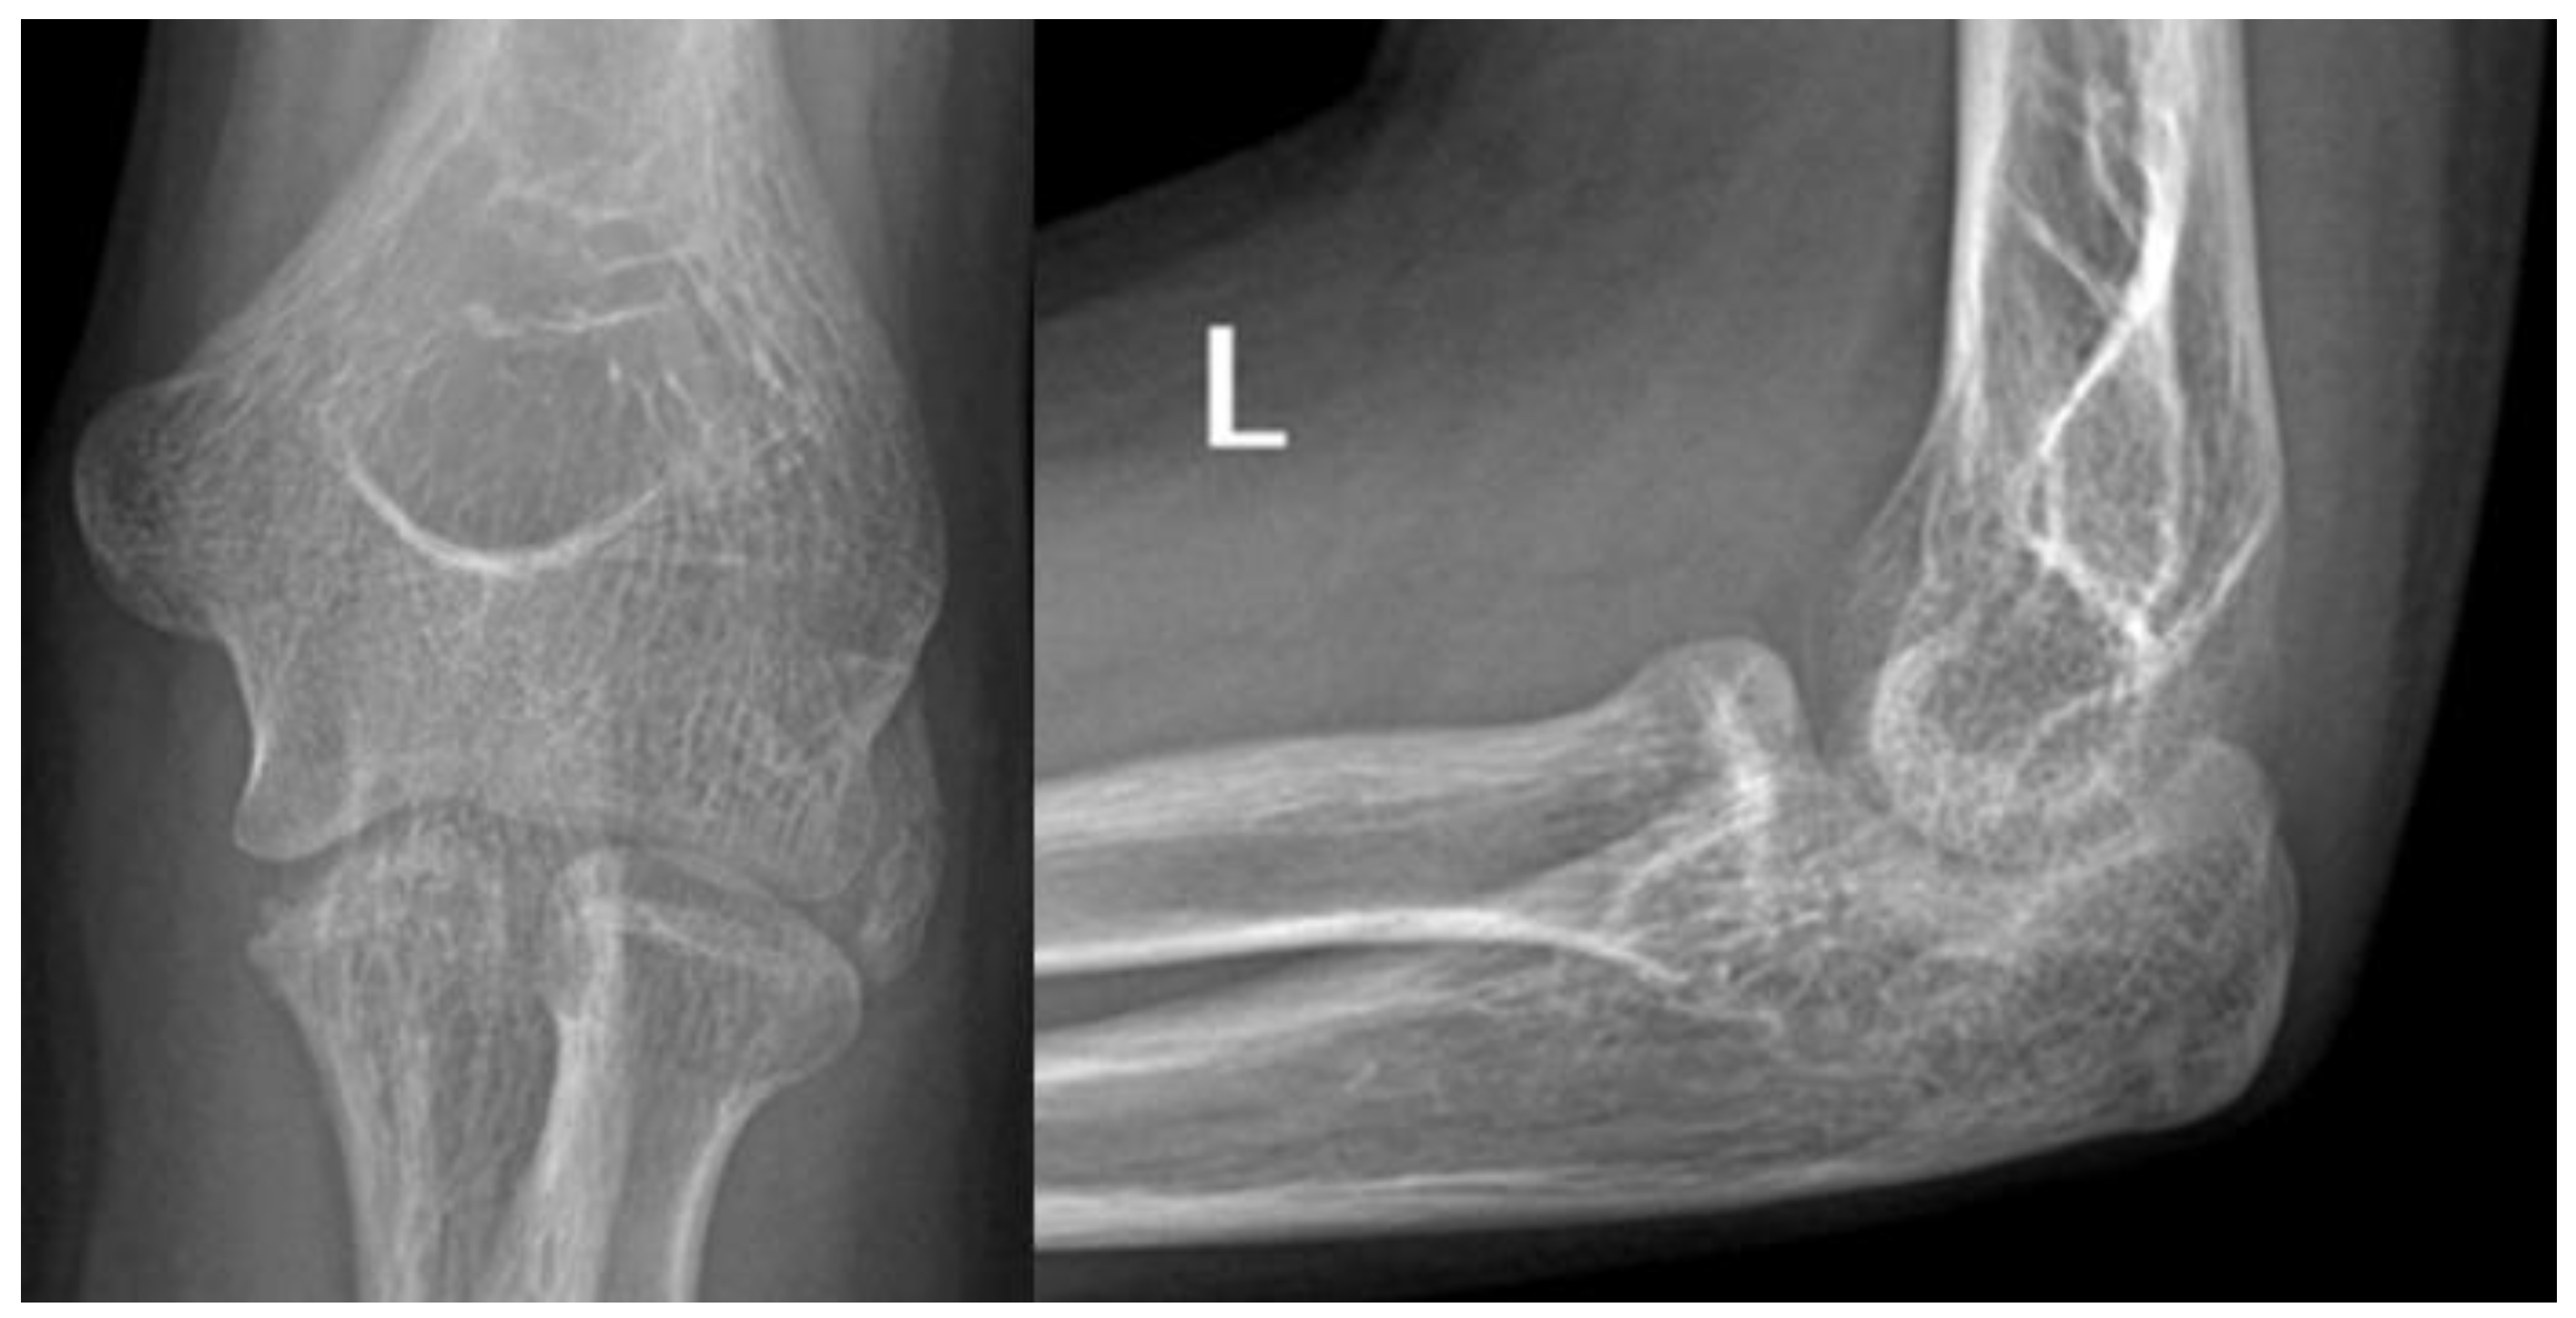

Figure 1.

Plain radiographs taken at the initial injury.